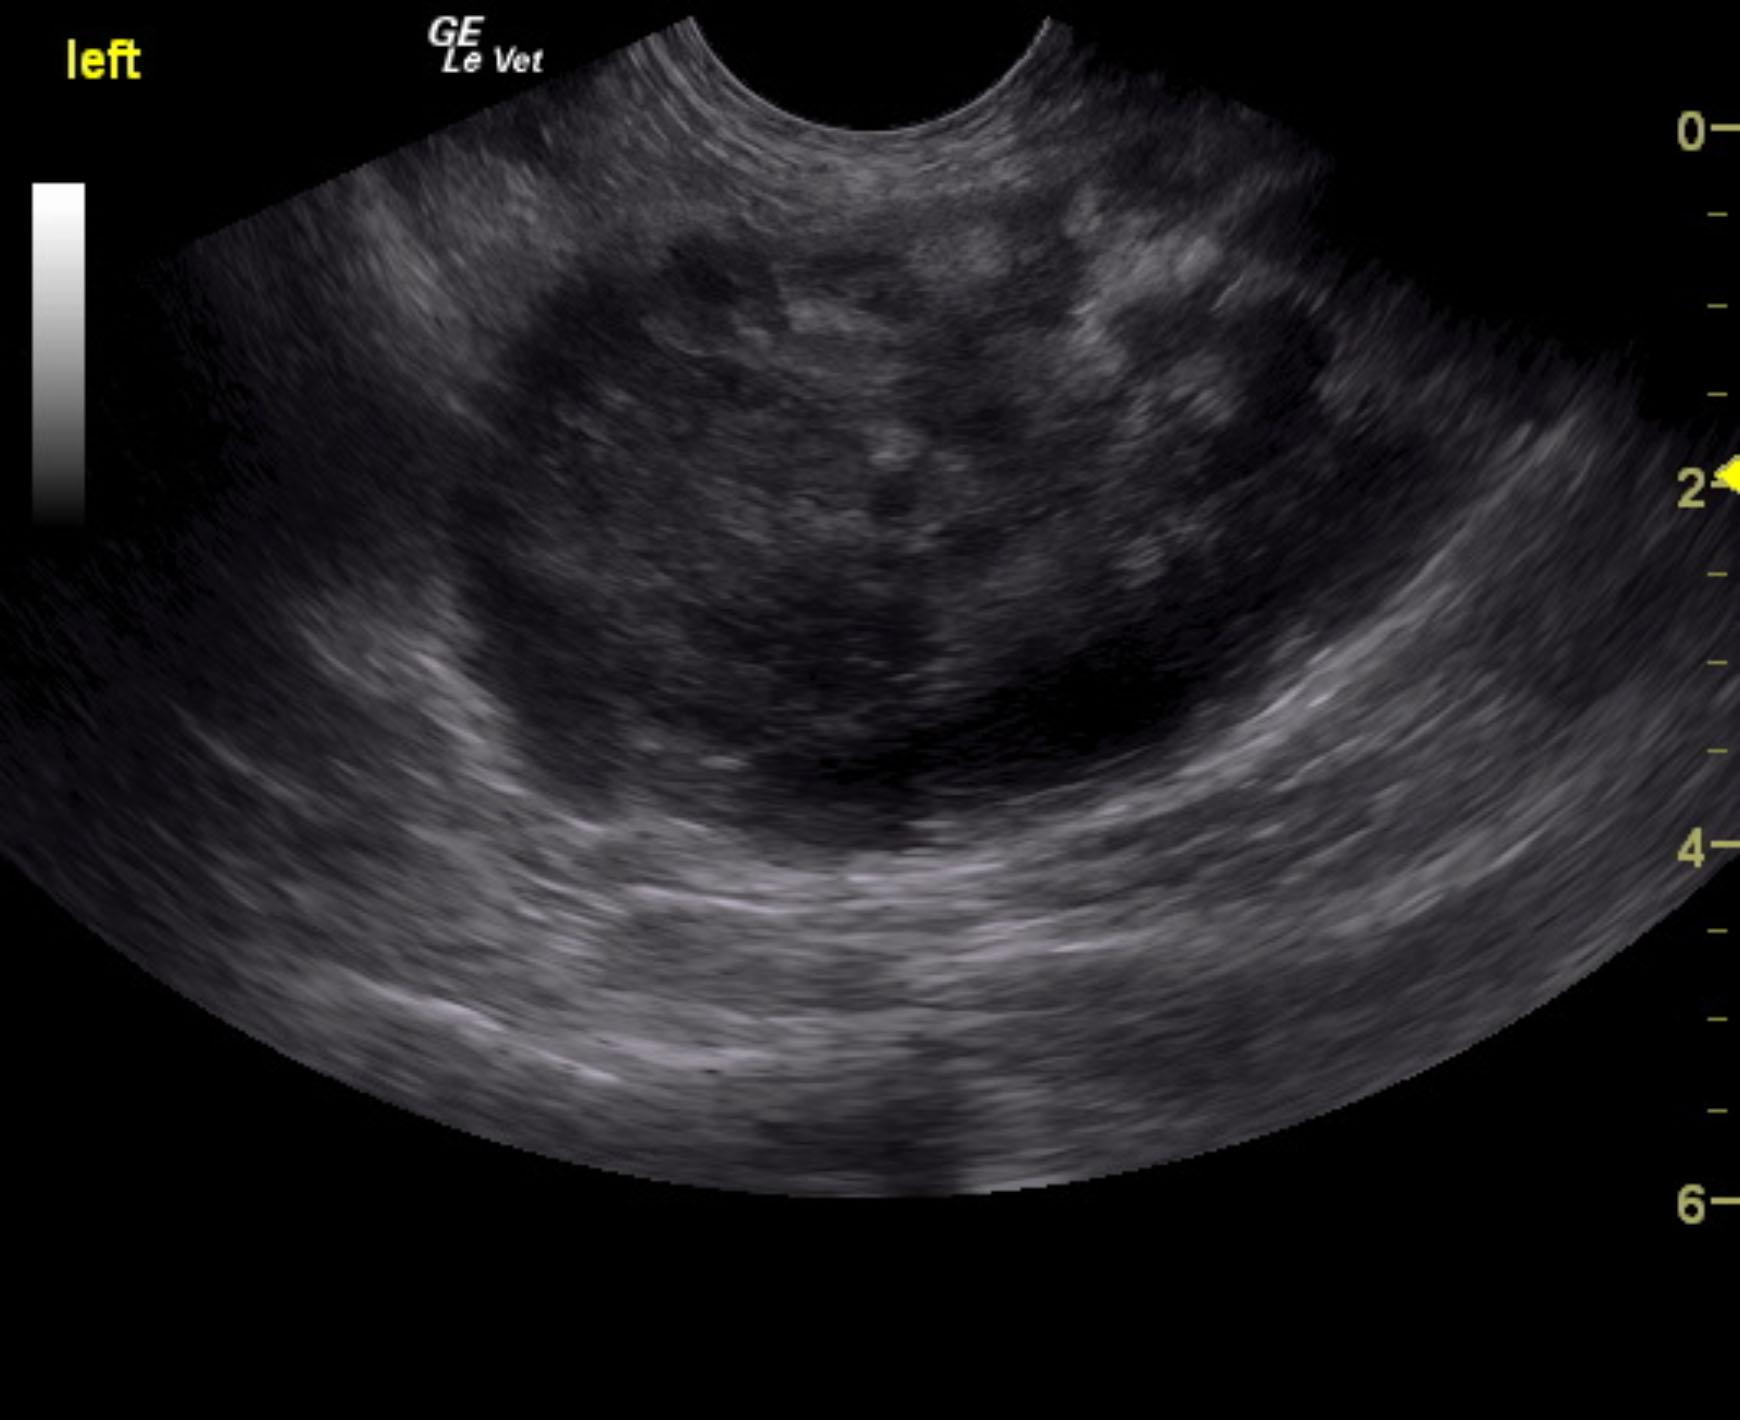

A 16-year-old SF DSH with a history of diabetes and hyperthyroidism was presented for evaluation of vomiting, diarrhea, and anorexia. Urinalysis showed SG of 1.017, proteinuria, and hematuria with negative bacterial growth. Coagulation panel was mildly elevated.

A 16-year-old SF DSH with a history of diabetes and hyperthyroidism was presented for evaluation of vomiting, diarrhea, and anorexia. Urinalysis showed SG of 1.017, proteinuria, and hematuria with negative bacterial growth. Coagulation panel was mildly elevated.